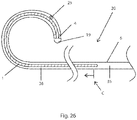

- FIG. 26 Another aspect of support spine 1 is illustrated in the example of Fig. 26 .

- Support spine 1 is drawn using hatch-marks to indicate that it is a different material than elongate member 6.

- the hatch-marks are not intended to limit support spine 1 to having cuts therein, as support spine 1 may, or may not, have cuts made therein or therethrough.

- Fig. 26 illustrates an embodiment of elongate member 6 with a distal portion having cuts made into it (although the individual cuts are not shown in the figure), starting at the point labeled with a "C".

- the support wire (or spine) extends proximally beyond point "C".

- support spine 1 is typically in contact with a wall of lumen 26, whereby electrical energy from elongate member 6 can flow through support spine 1 to energy delivery device 15, as described hereinabove.

- support spine 1 extends proximally beyond the cut portion of elongate member 6, (i.e. the proximal end of the support spine is proximal of the proximal end of the cut whereby the support spine overlaps with an uncut portion of the elongate member), whereby support spine 1 provides a backup or secondary electrical pathway in the case of a breakage or interruption in the pathway through the cut portion of elongate member 6.

- support spine 1 is connected at the distal end of the medical device 20 and extends proximally therefrom, while the proximal end of support spine 1 remains un-attached to, and independent of, elongate member 6 (or any other part of medical device 20), i.e. substantially only the distal end of support spine 1 is attached or otherwise connected to the medical device 20.

- support spine 1 extends proximally from the energy delivery device. While the embodiments of Figs. 1 to 27 show support spine 1 being joined to the center of electrode 19 of energy delivery device 15, alternative embodiments have support spine 1 attached or otherwise coupled to the device at other locations.

- an alternative embodiment comprises a closed-ended lumen with the support wire (or spine) being attached off-center.

- Another alternative embodiment comprises an open-ended lumen with the support wire being attached to a side-wall defining the lumen about the distal end of medical device 20.

- the proximal end of support spine 1 is independent of (or relative to) the side of lumen 26 (i.e. it is not fixed to the side of the lumen). This allows the proximal end of support spine 1 to be able to move longitudinally (and laterally) relative to the inner wall of the elongate member (e.g. a hypotube), which allows the distal end of medical device 20 (where the support spine 1 and elongate member 6 are joined) to bend or curve unimpeded by support spine 1. The ability of the distal end portion of medical device 20 to bend or curve facilitates advancing the device through tortuous vasculature and other body vessels.

- a difference in bend radius between the wall of elongate member 6 and support spine 1 arises from differences in the bend axis due to the wall thickness of the elongate member and the position of the support wire.

- the difference in bend radii results in different arc lengths for elongate member 6 and support spine 1.

- the support spine 1 were to be fixed at a proximal portion of medical device 20, the arc-lengths of elongate member 6 and support spine 1 would be fixed, and therefore the catheter curvature would be constrained.

- fixing the arc-lengths of elongate member 6 and support spine 1 is beneficial if such constraint of curvature of the medical device 20 is desirable (i.e. if a user desires to limit the amount of bending that is applied to a distal portion of medical device 20).

- typical embodiments of medical device 20 include a flexible elongate member 6 that defines a lumen 26, an independent support spine 1 being affixed to the distal end of medical device 20 and extending proximally within the lumen, and apertures 25 that may provide for delivering fluid at the distal end of medical device 20.

- the support spine 1 extends from the distal end within lumen distal portion 36 such that a lumen proximal portion 35 is substantially unobstructed (i.e. not obstructed by the support spine), thereby reducing and minimizing effects on fluid flow.

- cuts are made in the most distal 10 cm of the elongate member, the support spine 1 at the distal end of lumen 26 is about 10 or 11 cm in length and elongate member is from about 60 to about 120 cm in length.

- a distally attached support spine would partially obstruct fluid flow in the distal 10 cm of the 120 cm lumen.

- a possible alternative device could have support spine 1 attached at the proximal end of lumen 26 but for it to provide support at the distal end (having cuts therein) it would have to extend the entire length of the lumen (e.g.